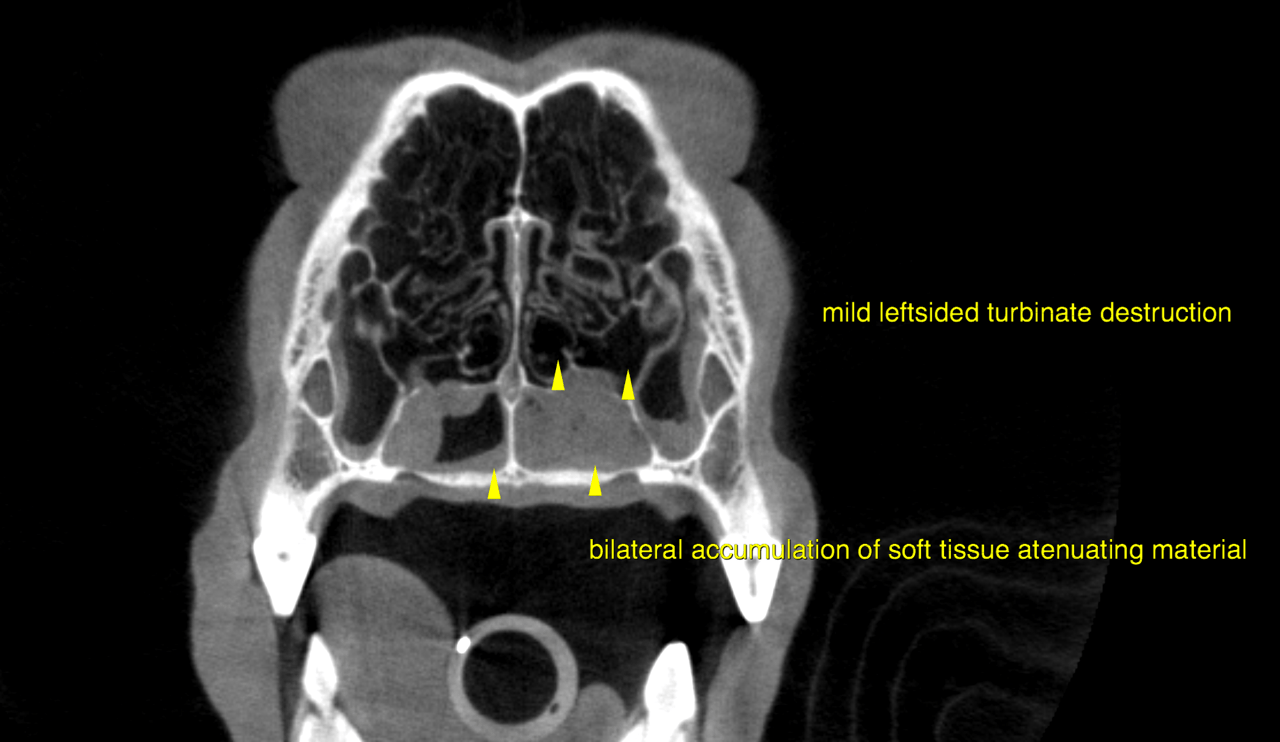

CT of the head, plain – The computed tomography reveals a moderate and mild amount of uniformly soft

tissue attenuating material in the dependent portion of the left and right nasal cavity

respectively. Part of the material is demarcated by a meniscus sign (horizontal viscous

fluid gas interface).

Mild thickening of the synovial lining and foci of mild turbinate destruction are noted

within the left nasal cavity. The overall findings are more severe on the left side.

As far as the anatomy is included there is no evidence of a mass lesion, bony lysis

and/or a foreign body.

The computed tomographic findings are compatible with bilateral unspecific chronic, mildly destructive rhinitis.